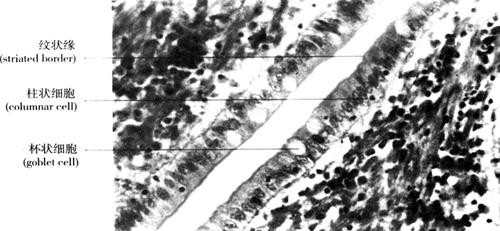

3.单层柱状上皮(simple columnar epithelium) 由一层棱柱状细胞构成,游离面有微绒毛。侧面观,为长方形,核椭圆形,近基底部(图2-9)。分布于胃、肠、子宫黏膜等处。以吸收、分泌为主。

图2-9 单层柱状上皮(400×)